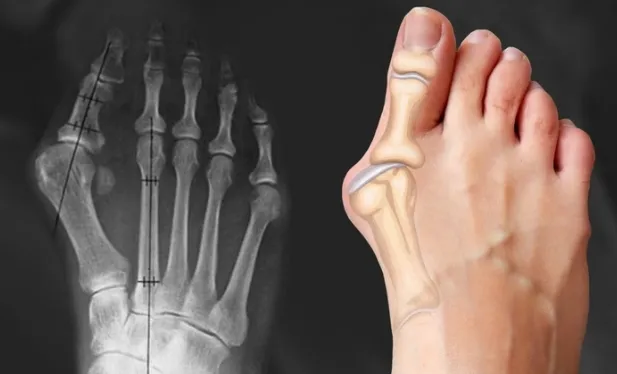

Массаж при вальгусной деформации стопы

Избавьтесь от боли и прогрессирующей деформации стопы, используя техники артикуляционно-рефлекторного массажа. Автор курса показывает, как работать с «косточкой» (hallux valgus), плоскостопием и сопутствующими изменениями в структуре стопы и голени.

В основе материала лежит остеопатический подход, направленный на мягкое воздействие и коррекцию без травмирующих манипуляций. Курс объясняет не только технику массажа, но и анатомию нижней конечности, что позволяет работать с причинами патологии, а не только с внешними симптомами. Помимо профессиональных приемов, разбирается методика самокоррекции стопы при помощи специальных упражнений. Материал будет полезен как практикующим массажистам для расширения набора инструментов, так и тем, кто хочет освоить безопасные техники для помощи себе и близким.